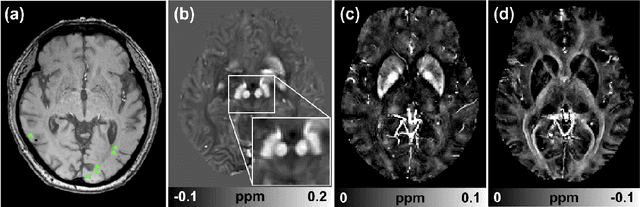

Abstract:In MRI, researchers have long endeavored to effectively visualize myelin distribution in the brain, a pursuit with significant implications for both scientific research and clinical applications. Over time, various methods such as myelin water imaging, magnetization transfer imaging, and relaxometric imaging have been developed, each carrying distinct advantages and limitations. Recently, an innovative technique named as magnetic susceptibility source separation has emerged, introducing a novel surrogate biomarker for myelin in the form of a diamagnetic susceptibility map. This paper comprehensively reviews this cutting-edge method, providing the fundamental concepts of magnetic susceptibility, susceptibility imaging, and the validation of the diamagnetic susceptibility map as a myelin biomarker. Additionally, the paper explores essential aspects of data acquisition and processing, offering practical insights for readers. A comparison with established myelin imaging methods is also presented, and both current and prospective clinical and scientific applications are discussed to provide a holistic understanding of the technique. This work aims to serve as a foundational resource for newcomers entering this dynamic and rapidly expanding field.